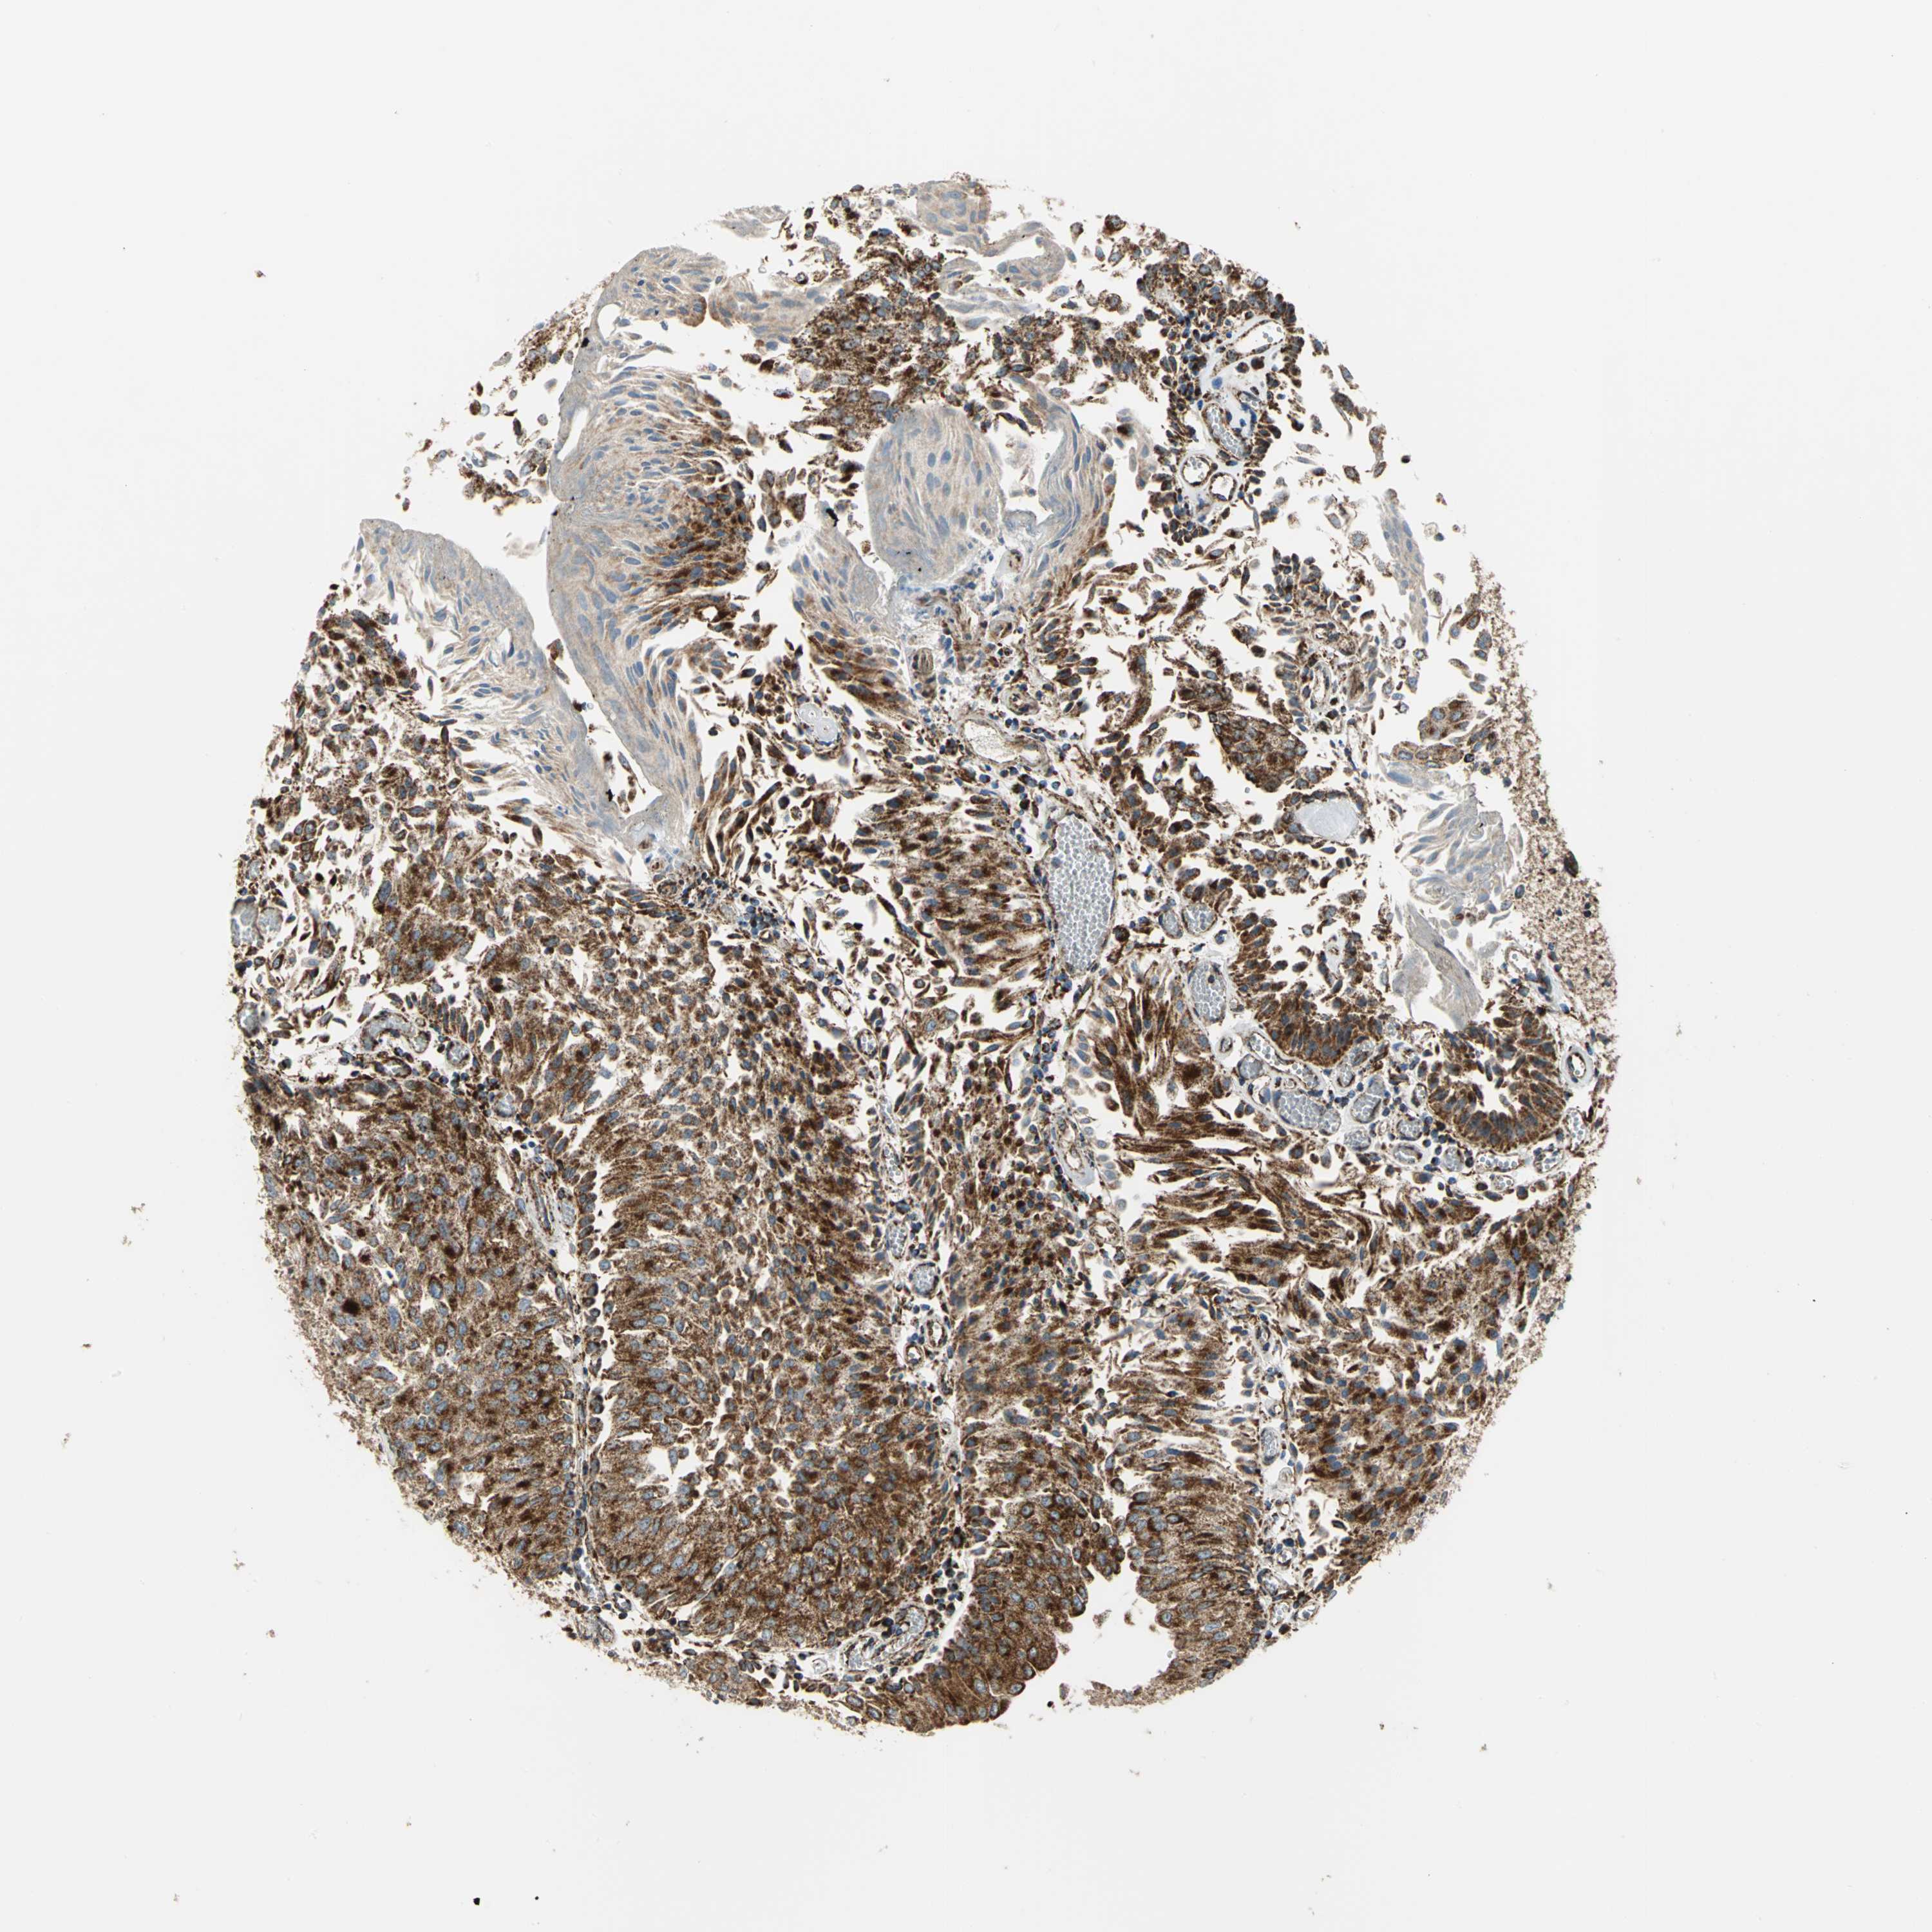

UROTHELIAL CANCER - Protein expressioni

A mouse-over function shows sample information and annotation data. Click on an image to view it in a full screen mode. Samples can be filtered based on level of antibody staining by selecting one or several of the following categories: high, medium, low and not detected. The assay and annotation is described here.

Note that samples used for immunohistochemistry by the Human Protein Atlas do not correspond to samples in the TCGA dataset.

Antibody stainingi

Antibody staining in the annotated cell types in the current human tissue is reported as not detected, low, medium, or high, based on conventional immunohistochemistry profiling in selected tissues. This score is based on the combination of the staining intensity and fraction of stained cells.

Each image is clickable and will lead to virtual microscopy that enables deeper exploration of all samples and also displays staining intensity scores, fraction scores and subcellular localization as well as patient and tissue information for each sample.

Antibody HPA006083

Antibody HPA007830

Staining

High

Medium

Low

Not detected

Intensity

Strong

Moderate

Weak

Negative

Quantity

>75%

75%-25%

<25%

None

Location

Nuclear

Cytoplasmic/membranous

Cytoplasmic/membranous,nuclear

Urothelial carcinoma, High grade

Urothelial carcinoma, Low grade